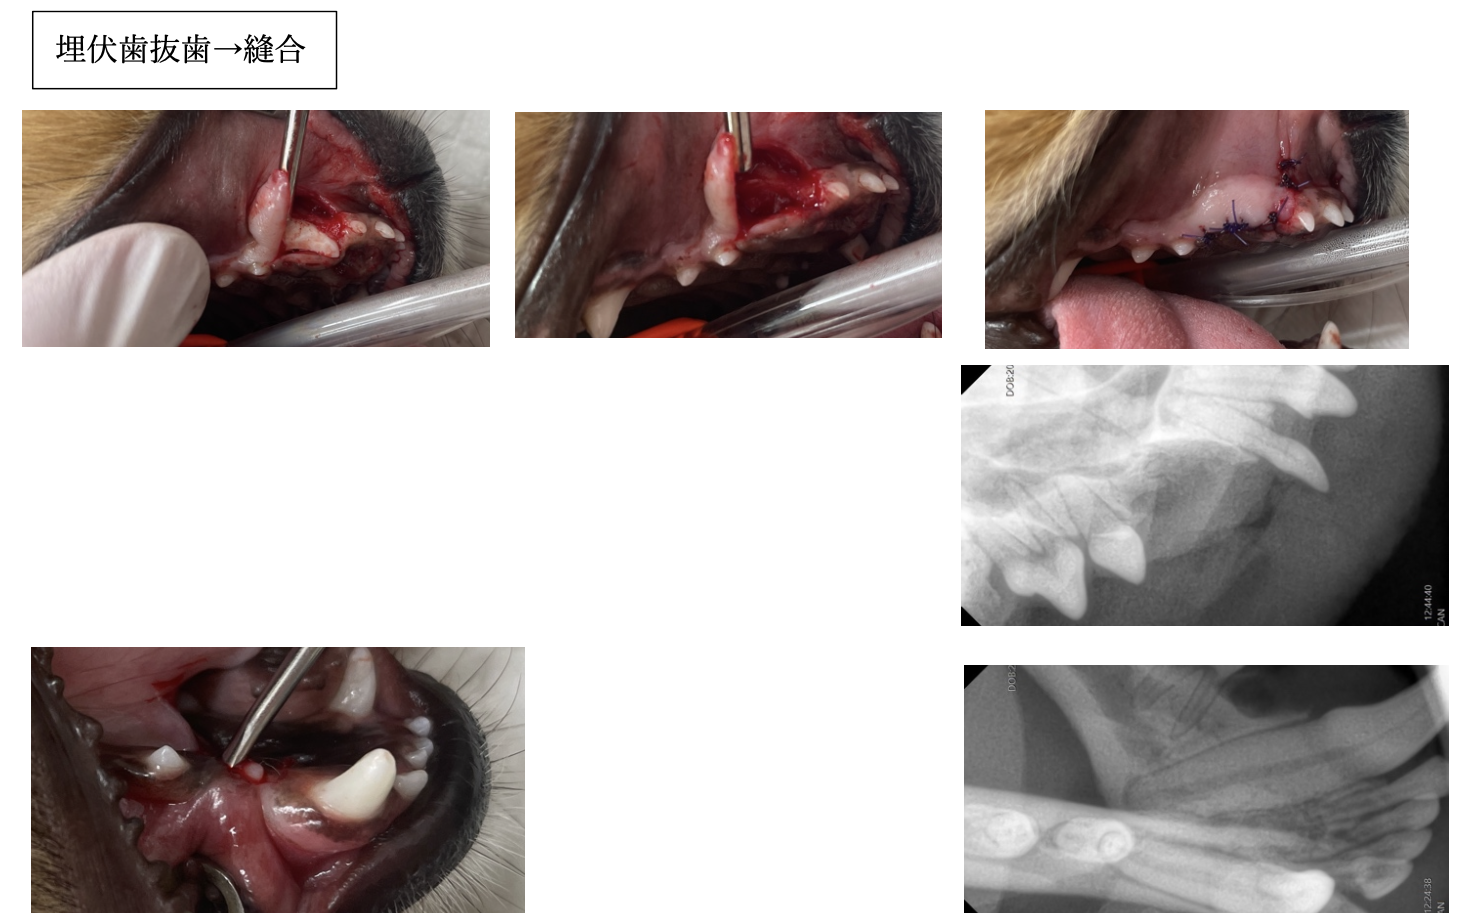

歯肉を切開すると、写真のように歯が歯肉の下に埋まっていたことがわかります。

抜歯後、残った歯の一部がないか歯科レントゲン検査も実施します。